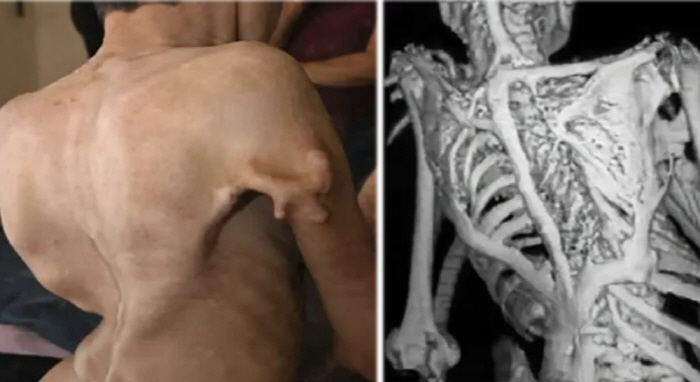

라자스탄 패트리카 등 현지 매체들에 따르면 인도 AIIMS 조드푸르 병원 의료진은 라자스탄주 자이살메르 지역에 거주하는 9세 소년이 극히 드문 유전 질환인 'Fibrodysplasia Ossificans Progressiva(FOP)'로 진단됐다고 밝혔다.

이 질환은 근육과 인대가 점차 뼈로 변하면서 몸이 굳어가는 특징으로, 이른바 '돌 인간 증후군'으로 불리기도 한다. 현지 의료진은 약 200만 명 중 1명꼴로 발생하는 매우 희귀한 질환이라고 설명했다.

의료진은 "이 질환은 관절 주변에 새로운 뼈 조직이 형성되면서 점차 신체 움직임이 제한되는 것이 특징"이라며 "병이 진행될수록 환자는 움직일 수 없게 돼 사실상 살아 있으면서도 몸이 굳어가는 상태에 놓이게 된다"고 밝혔다.